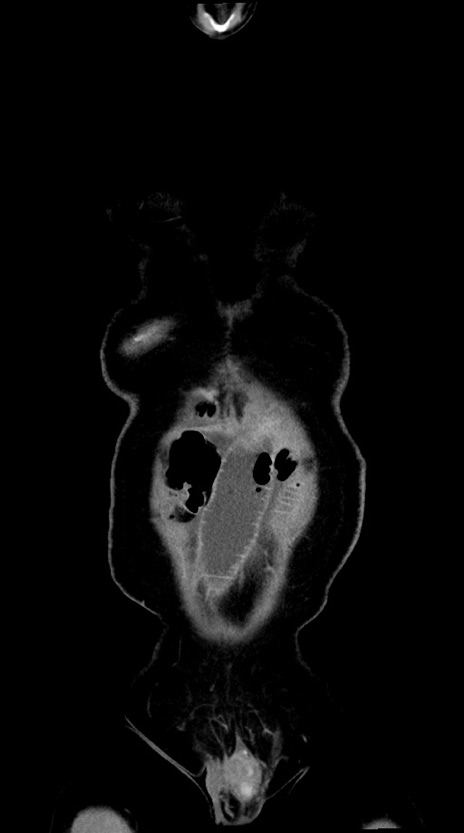

横断像

【症例】60歳代男性

【主訴】嘔吐

【現病歴】胃癌にて胃全摘後。食思不振が悪化し、夜中に嘔吐することがある。

【既往歴】胃癌、胃全摘、脾摘、胆摘後

【データ】WBC 5900、CRP 10.56